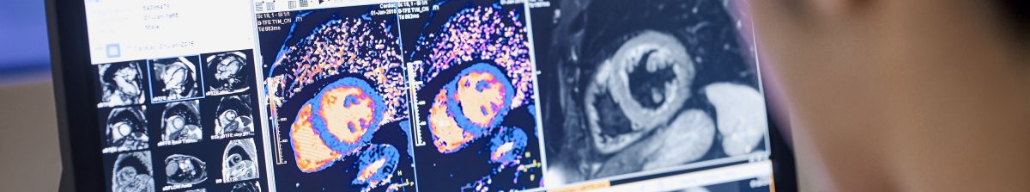

МРТ сердца проливает свет на вакцин-ассоциированный миокардит

Фото из открытого источника (Яндекс-картинки)

При миокардите, ассоциированном с вакцинацией, отмечается картина повреждения на МРТ сердца аналогичная миокардиту, вызванному другими причинами, но нарушения менее серьезны, согласно новому исследованию, опубликованному в журнале Radiology и на медицинском портале Medical Xpress1.

МРТ сердца играет важную роль в оценке острого миокардита с беспрецедентной способностью к неинвазивной характеристике ткани миокарда. Понимание характера и степени повреждения миокарда и его последствий позволит улучшить уход за этими пациентами и может помочь решить проблему выбора в отношении вакцинацинации.

Результаты МРТ при миокардите, ассоциированном с вакцинацией, включали позднее повышение уровня гадолиния у 17 (81%) и дисфункцию левого желудочка у 6 (29%). МРТ сердца показала, что по сравнению с другими причинами миокардита, у пациентов с миокардитом, связанным с вакцинацией, были меньшие функциональные нарушения и менее обширные участки повреждения миокарда.